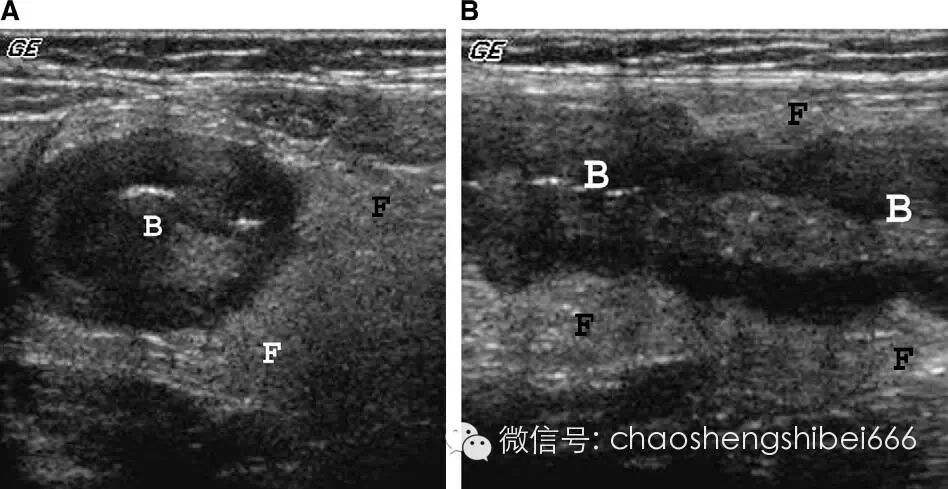

回结肠肠套叠超声声像图上可见一个分层的肿块或可见肿块周边低回声的水肿的肠壁包裹(图6)。套叠内部中心的高回声是病灶内包裹的肠系膜脂肪,在其内经常可见淋巴结,多呈小于25px的椭圆形低回声结构(图7)。虽然没有超声检查征象可以肯定不能进行随后的钡灌肠治疗,但是超声检查的一些结果可以提示灌肠较难复位或容易合并穿孔。这些结果包括多普勒评价套叠的肠壁缺血以及肠套叠层那出现局限性积液。

很多其他疾病多被误诊为回结肠肠套叠,小肠的肠套叠与回结肠的肠套叠相似,但直径比较小且多为一过性(图8)。能导致肠壁增厚的疾病超声表现也可相似,包括炎症性肠病,肠淋巴瘤以及肠壁内出血。

6 4月大男婴肠套叠声像图呈低回声的面包圈征(箭头),中心 可见肠系膜脂肪强回声。L肝脏

7 3岁男孩肠套叠声像图(箭头),套入部肠系膜叠内可见多个发淋巴结(星号)